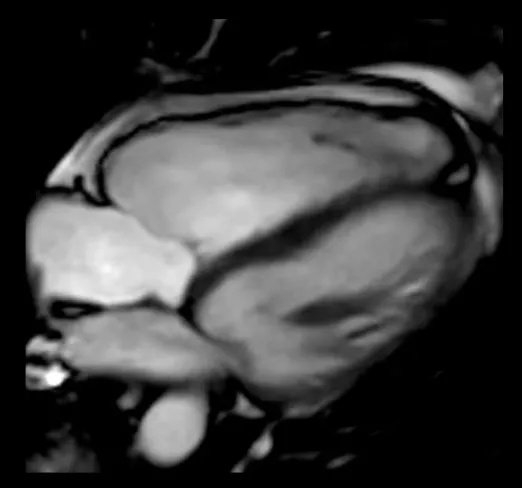

Figure 1

Pathophysiologic Subdivision of Tricuspid Regurgitation. Primary tricuspid regurgitation is caused by abnormalities/damage on the tricuspid valve apparatus (A) (e.g., prolapse of the leaflet or endocarditis). Left heart related tricuspid regurgitation and precapillary pulmonary tricuspid regurgitation (B) are caused by dilation of the right ventricle, papillary muscle displacement and tethering of the tricuspid valve leaflets with malcoaptation. In isolated tricuspid regurgitation (C) the tricuspid annulus is pronouncedly dilated due to dilation of the right atrium in the presence of atrial fibrillation or diastolic dysfunction.

Left-heart related tricuspid regurgitation (LH-TR) is the most common form of FTR caused by left-sided valvular and myocardial disease associated with increased left atrial pressure, pulmonary hypertension and increased RV afterload which leads to RV dilation in particular at the basal level, tricuspid leaflet tethering, tricuspid annulus dilation and leaflet malcoaptation (Figure 1B) (14). Compared to healthy valves the annulus becomes more planar, circular and dilated. Due to RV dilation, TR regurgitation results in a larger RV eccentricity index. Depending on the presence of pulmonary hypertension the RV becomes more elliptical, emphasizing valvular tethering (9, 10).

The RV shows a midventricular dilation, a dilation of the tricuspid annulus and the right atrium (Figure 1B). However, leaflet tethering due to lateral and apical papillary muscle displacement seems to be the dominant mechanism in pulmonary hypertension (21, 22).